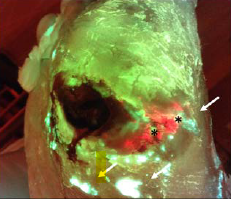

Detection of bacterial fluorescence from in vivo wound biofilms using a point-of-care fluorescence imaging device

Lopez, AJ et al. Int Wound J 2021